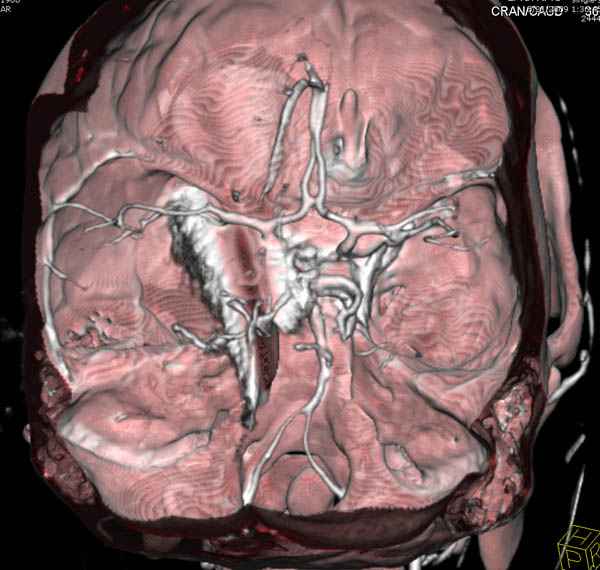

В своих выступлениях я рассказывал, что наши центры в мирное время по пенетрирующим травмам не уступает Ираку или Афганстану, и вот недавно к нам поступила больная 22 лет, травма "ножом в глаз" от бывшей подруги нынешнего "бой френда".

При поступлении в сознании, жаловалась на неприятные ощущения в глазнице.

По протоколу сделаны все необходимые исследования: рентген, ангиограмма с 3Д реконструкцией, где обнаружили что все жизненно важные сосуды не задеты, даже некоторые "сидят" изгибаясь на ноже.

Одним махом нож удалить не удалось, пришлось раскачать и потом двумя руками удалили нож. Рана без кровотечения, обработана и зашита.